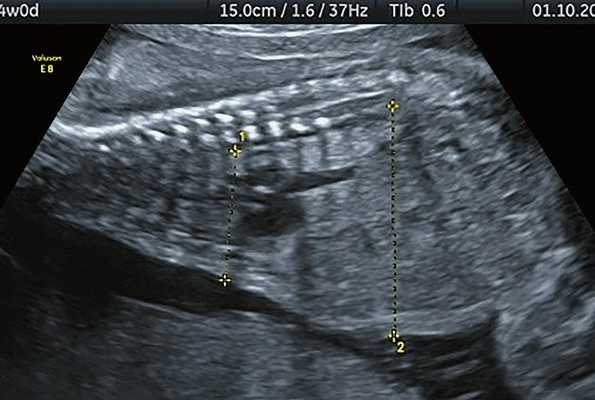

б) Узкая грудная клетка.

в) Узкая грудная клетка.

г) Уплощенные тела позвонков; показано увеличенное расстояние между позвонками.

Основные ультразвуковые характеристики плодов, полученные при нашем исследовании, отображены в таблице 1 и на рис. 1-4.

| Срок беременности | Голова | Грудная клетка | Конечности | Дополнительные находки |

|---|---|---|---|---|

| Набл. 1. 24,3 нед. | БПР - 25,3 нед. ОГ - 24,6 нед. Аномально повышенная бороздчатость и выпуклость извилин нижнемедиальной поверхности височных долей (рис. 1а). | Торакоабдоминальное соотношение - 66,7% (рис. 1б) Длина ребра - среднее для 16 нед. | Бедренная кость 19,6 мм (47,8% от должной), изогнута ("телефонная трубка") (рис. 1в). Остальные кости - среднее для 15 нед. | Уплощенные тела поясничных позвонков. |

| Набл. 2. 20,3 нед. | БПР - 21,5 нед. ОГ - 20,3 нед. Уплощенный затылок. Выпуклые темпоральные бугры (рис. 2а). Аномально повышенная бороздчатость и выпуклость извилин нижнемедиальной поверхности височных долей (рис. 2б). | Торакоабдоминальное соотношение - 63,3% (рис. 2в) Окружность груди - среднее для 18 нед. Длина ребра - среднее для 15 нед. | Бедренная кость 17,7% (61% от должной), изогнута ("телефонная трубка") (рис. 2г). Остальные кости - среднее для 13-14 нед. | Гипоплазия костей носа. |

| Набл. 3. 24 нед. | БПР - 30 нед. ОГ - 27,2 нед. Уплощенный затылок. Выпуклые темпоральные бугры (рис. 3а). Аномально повышенная бороздчатость и выпуклость извилин нижнемедиальной поверхности височных долей (рис. 3б). | Торакоабдоминальное соотношение - 56,6% (рис. 3в) Окружность груди - среднее для 20 нед. Сердце/грудь (см 2 ) - индекс 0,6. | Бедренная кость 23,1 мм (57% от должной), изогнута ("телефонная трубка") (рис. 3г) Остальные кости - 50% для 15-16 нед. Нормальная установка пальцев кисти (рис. 3д). | Многоводие. |

| Набл. 4. 26,5 нед? | БПР - 22,6 нед. ОГ - 22,6 нед. Форма - трилистник (рис. 4а). Боковые желудочки - 22 мм, высокий лоб, расширенный родничок, сагиттальный шов (рис. 4б). | Торакоабдоминальное соотношение - 65,7% (рис. 4в). Окружность груди - среднее для 23 нед. Колоколообразная форма. | ДБ - 23 мм (51% от должной). Остальные кости - 50% для 15-17 нед. Нормальная установка пальцев кисти (рис. 4б). | Уплощенные тела поясничных позвонков (рис. 4г). |

Примечание. БПР - бипариетальный размер, ОГ - окружность головы, ДБ - длина бедренной кости.

Длину бедренной кости оценивали по региональным нормативам, а остальные кости - по Ph. Jeanty. Окружность грудной клетки оценивали по U. Chitkara и соавт. [14], длину ребер - по A.Z. Abuhamad [15].

УЗИ позволяет выделить группу скелетных дисплазий плода с сужением грудной клетки, являющимся одним из важных прогностически неблагоприятных признаков независимо от нозологической формы остеохондроплазий. Во всех представленных нами случаях у плодов отмечены микромелия и гипоплазия грудной клетки (окружность грудной клетки была менее 5% для гестационного срока, а торакоабдоминальное соотношение было в пределах 56,6-67,6%).